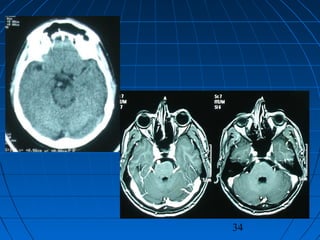

 42 yaşında erkek hasta42 yaşında erkek hasta

 BaşağrısıBaşağrısı (kronik)(kronik)

 Nörolojik olarak intaktNörolojik olarak intakt

34